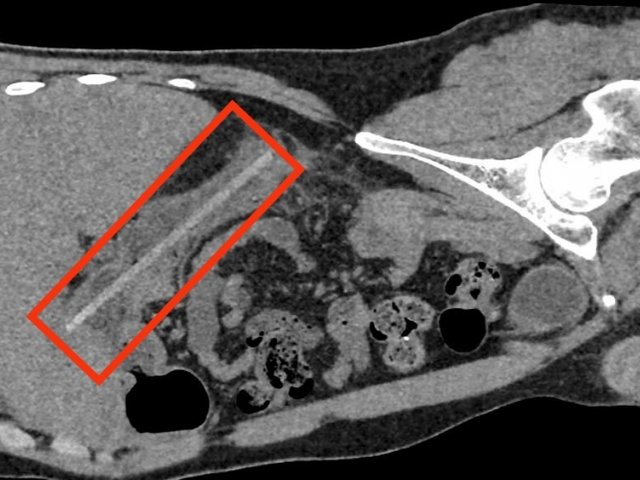

Hy hữu vụ cứu bệnh nhân nuốt chiếc đũa dài 18cm vào bụng, gây thủng tá tràng

Nam thanh niên vô tình nuốt chiếc đũa cách đây 3 tháng nhưng chủ quan không đi khám. Cơn đau ngày càng nghiêm trọng nên anh đã được người nhà đưa đến bệnh viện để cấp cứu...